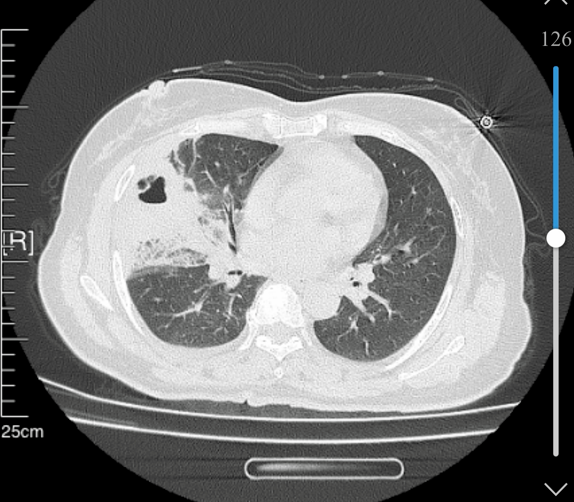

張姨(化名)近期反復(fù)出現(xiàn)胸痛不適,伴隨輕微咳嗽、乏力,自認(rèn)為年紀(jì)大了心臟易出問(wèn)題,便在家自行含服救心丸,可癥狀不僅沒(méi)有緩解,反而逐漸加重,還出現(xiàn)發(fā)熱、呼吸不暢等情況。家人急忙將其送至我院,醫(yī)生詳細(xì)問(wèn)診后,并未盲目排查心臟問(wèn)題,而是及時(shí)安排胸部CT檢查,最終明確診斷為右肺中葉膿腫伴嚴(yán)重感染,揪出了“偽裝”成心臟病的真兇。

據(jù)了解,肺膿腫是肺部組織因細(xì)菌感染形成的化膿性病變,若不及時(shí)清除膿液、控制感染,可能引發(fā)膿胸、敗血癥等嚴(yán)重并發(fā)癥,危及生命。由于張姨的膿腫位置較深,單純藥物治療難以直達(dá)病灶,我院呼吸內(nèi)科團(tuán)隊(duì)迅速評(píng)估病情,制定了微創(chuàng)支氣管肺泡灌洗個(gè)性化治療方案,無(wú)需開(kāi)刀,僅通過(guò)支氣管鏡經(jīng)鼻腔、咽喉進(jìn)入氣道,精準(zhǔn)到達(dá)病灶,徹底沖洗、抽吸膿液及炎性分泌物,再輔以針對(duì)性抗感染治療。

整個(gè)操作微創(chuàng)無(wú)痛、耗時(shí)短、創(chuàng)傷小,術(shù)后張姨無(wú)明顯不適感,當(dāng)天胸痛、胸悶癥狀便明顯減輕,體溫也逐漸恢復(fù)正常。經(jīng)過(guò)后續(xù)鞏固治療,復(fù)查CT顯示肺膿腫基本吸收、炎癥完全消退,張姨順利康復(fù)出院。